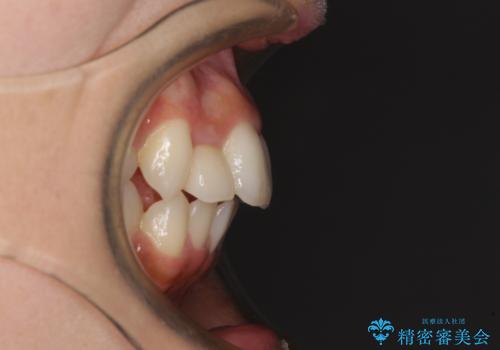

- 上下前歯のデコボコを気にして来院された患者様です。

前歯のセラミックが装着されている歯は、歯根が短くなっており、他院では抜けてしまうので矯正はできないと言われていたようです。

患者様と相談し、抜けてしまった場合にはインプラントあるいはブリッジによる補綴治療が必要となることを確認し、極力歯根に負担のかからないような仕上がりで治療を進めて行くこととしました。

デコボコを解消には、IPR(歯と歯の間を削る)をメインに歯列排列を設計し、インビザラインにて矯正治療を行うこととしました。

レントゲン写真上では、矯正治療前後で歯根長さに大きな違いはなく、抜歯を回避することができました。

上顎内側に転位している前から2番目の歯は移動が難しく、無理矢理歯根全体を動かそうと設計すると、歯肉退縮・歯髄壊死・歯根吸収といった危険性が増すため、無難なゴールにて治療を終えることとなりました。